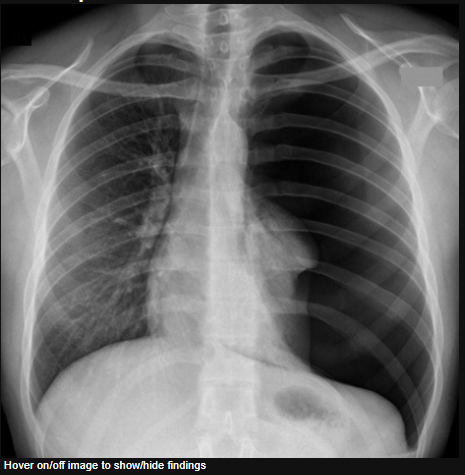

The trachea is deviated to the left. It is possible to say this with confidence because the patient is not rotated - the spinous processes lie midway between the medial ends of the clavicles. Any deviation of the trachea from the midline is therefore genuine.

Whenever you see deviation of the trachea, ask yourself if it has been PUSHED or PULLED. Here the trachea has been PULLED to the left by the volume loss in the left upper lobe caused by localised lung fibrosis. In this case this was due to previous radiation treatment.